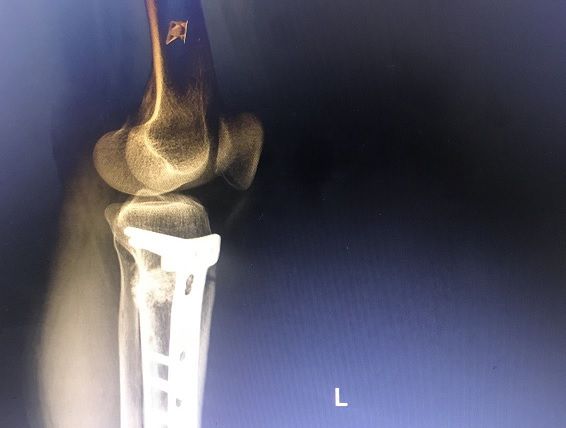

Osteotomi ameliyatı

Close wedge

Bu operasyonda, bacaktaki dizin sağlıklı kısmının altından veya uyluğun alt kısmından üçgen veya kama şeklinde bir kemik çıkarılır ve boşluk kapatıldıktan sonra, uzvun uzantısı düzeltilerek bir cihazla sabitlenir. (Çıkarılan kemik miktarı deformitenin büyüklüğüne bağlıdır ve farklı şekilde modifiye edilmesi gerekir). Bu yöntemde vücut biraz daha kısalır.